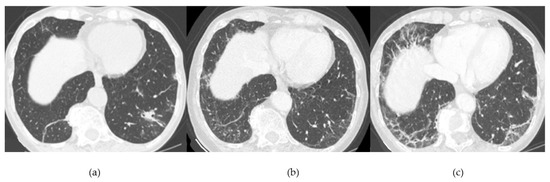

- Asymptomatic/occult ILD (minimal or absent changes seen on HRCT) [43];

- Acute or rapidly progressive ILD (acute interstitial pneumonia and radiological evidence of acute respiratory distress syndrome (ARDS) due to diffuse alveolar damage) [44];

- Chronic progressive fibrosing ILD (reticulation and honeycombing with minimal GGOs on HRCT scans, related to fibrotic NSIP or UIP) [43];

Acute Type